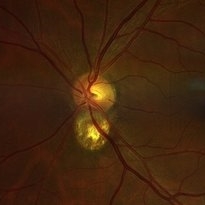

Colobomatous Optic Disc Maculopathy

Colobomatous Optic Disc Maculopathy

Feb 13 2020 by Yoshihiro Yonekawa, MD, FASRS

Beautifully focused fundus photograph of a teenage girl with submacular fluid from a colobomatous optic disc.

Photographer: Netanya Lerner, COA, Wills Eye Hospital/Mid Atlantic Retina

Imaging device: Topcon

Condition/keywords: chorioretinal coloboma, coloboma of optic disc, congenital optic nerve pit, subretinal fluid